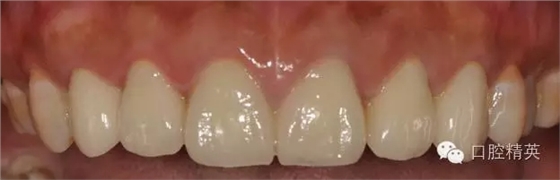

修復體完成口內(nèi)照片